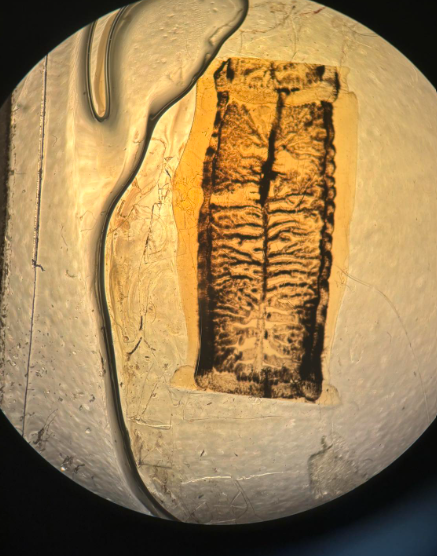

taenia saginata proglotyd przejrzały

taenia solium proglotyd przejrzały